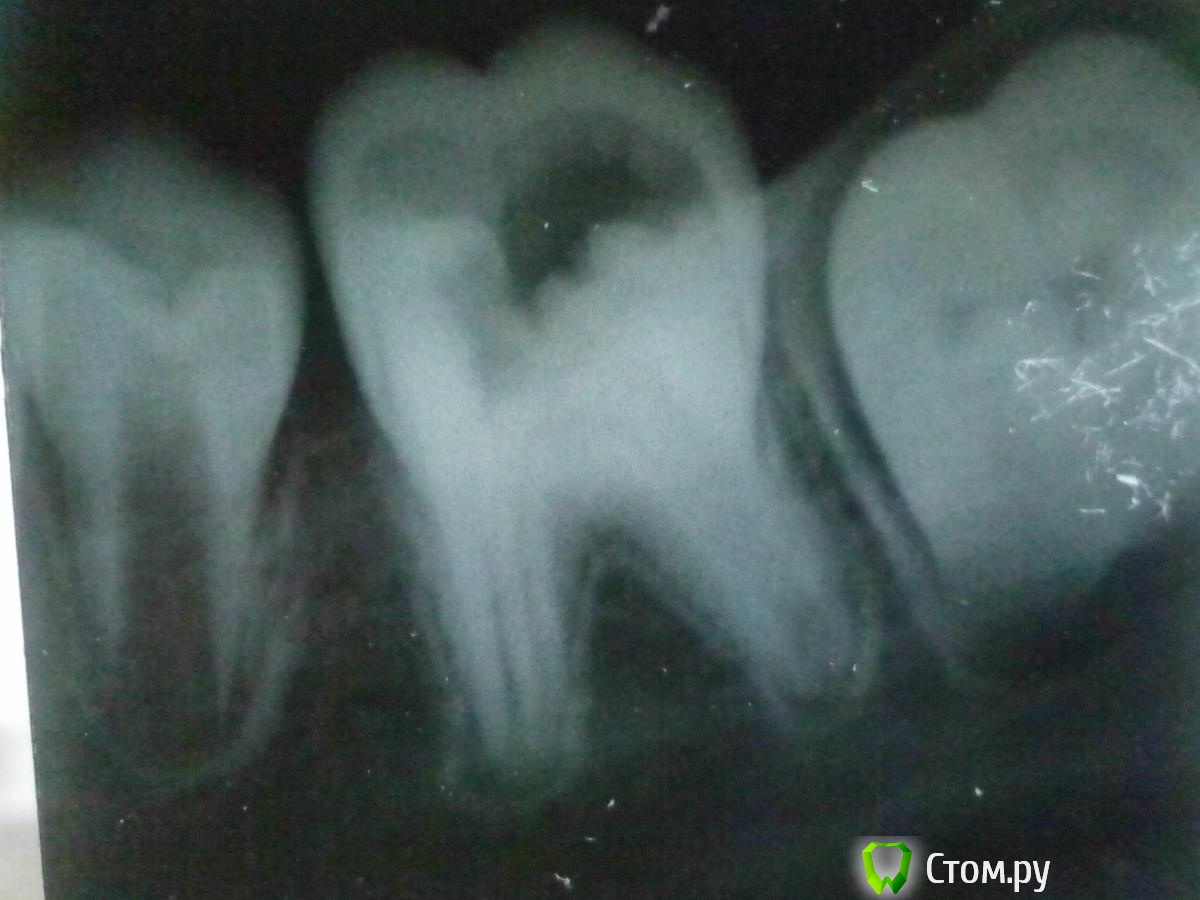

korostell Опубликовано 29 января, 2014 Поделиться Опубликовано 29 января, 2014 Разрешите продолжить тему.Пациент 14 лет, кариозная полость 3.7. Жалоб нет, ранее не болел. При зондировании "проваливаюсь" в полость зуба, боли нет. Раскрываю полость, ампутация- норм., экстирпация болезненна, но обходимся без анестезии. Каналы широкие и в каналах как будто эксудат, но без запаха. Промываю, промываю все равно отток незначительный есть. Честно говоря, я даже растерялась. Детей принимаю, но с несформированными попадаются редко. В общем я положила ему Метапекс в каналы (не глубоко) и отправила на рентген.Подскажите пожалуйста, как мне лучше поступить дальше. Прорута нет, к сожалению. Можно ли запломбировать Метапексом? Спасибо! Ссылка на комментарий

Scrabble Опубликовано 29 января, 2014 Поделиться Опубликовано 29 января, 2014 Снимок есть? Ссылка на комментарий